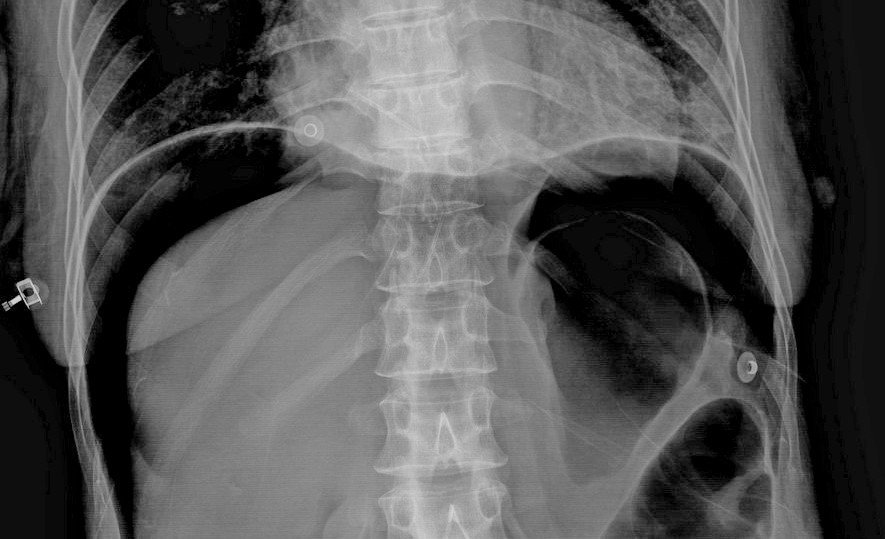

Additional abdominal radiograph : upright view

• Crescentic free air under both dome of the diaphragm, representing subdiaphragmatic free gas

Subdiaphragmatic free gas:

• Air under the diaphragm and air in the lungs outline the diaphragmatic contour well

• As little as 1 ml of free air can be detected but the patient may be needed to be kept in upright position for about 10 minutes for the air to rise